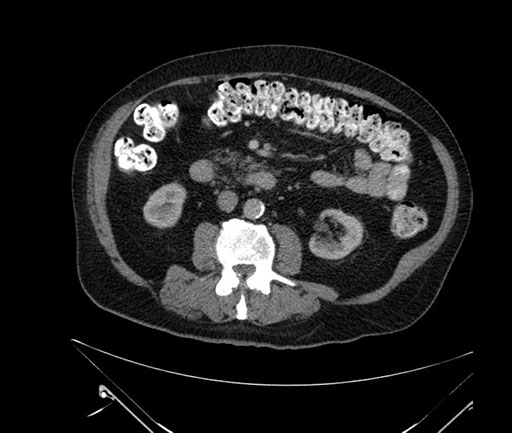

Axial - stented